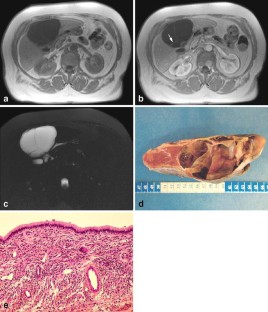

Magnetic resonance imaging (MRI) and magnetic resonance cholangio-pancreatography (MRCP) features were analyzed in the diagnosis of seven surgically resected hepatobiliary cystic tumors with reference to histopathological data. Homogeneity, size, location, signal intensity, presence or absence of septa and/or nodules and MRCP features of the lesions were studied. Histological evidence demonstrated six biliary cystadenoma (BCA) including four pseudo-ovarian stroma (POS) and one biliary cystadenocarcinoma (BCAC). Cystic lesions (3–15 cm in diameter) were homogeneous in the six BCA, heterogeneous in the one BCAC, and were located in the left and right liver, respectively. On T2-weighted images all lesions were hyperintense. On T1-weighted images hypointensity was found in three BCA (all serous fluid, including one POS), isointensity was found in the three others (two mucinous and one hemorrhagic fluid, including three POS) and in the one BCAC (containing mucinous fluid). Septas were present in all cases and nodules only in the one BCAC. On MRCP a hyperintense cystic lesion was found in all cases and a bile ducts dilatation in two BCA and the one BCAC. Gadolinium-enhanced MRI in combination with MRCP is a valuable tool for the diagnosis of BCA or BCAC. However, no specific information is gained for POS detection.

Fig. 4